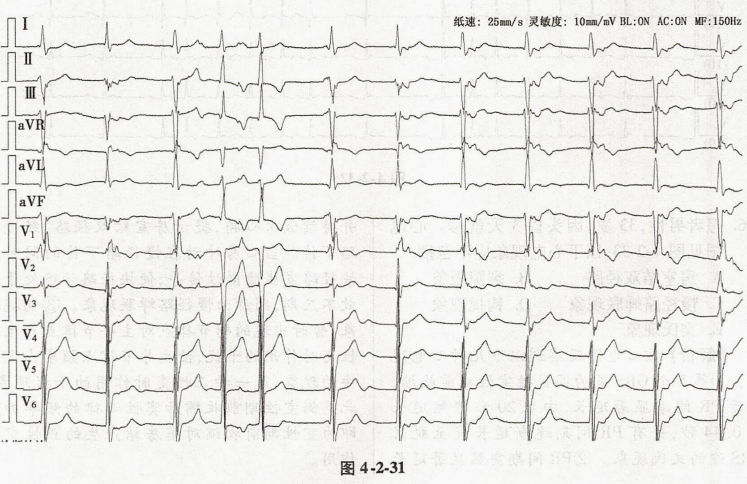

患者男性,75岁,临床诊断为老年退行性心脏病,主动脉瓣重度关闭不全,心功能3级。心电图见图4-2-31,准确而完整的诊断应为

-